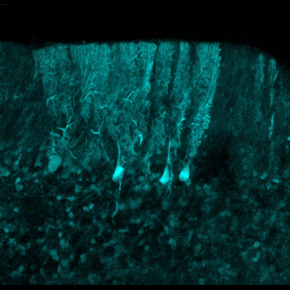

Adapter nos mouvements suite à des blessures ou des entrainements intensifs est possible grâce au traitement et au stockage d’une multitude d’informations sensorielles, proprioceptives et motrices par le cortex cérébelleux. En cartographiant les connexions synaptiques dans le cervelet de souris entrainées ou lésées, des scientifiques de l'Institut des neurosciences cellulaires et intégratives (INCI | CNRS), entre autres, montrent que les réseaux neuronaux du cortex cérébelleux stockent les adaptations sensorimotrices spécifiques à chaque individu. Ces résultats sont publiés dans la revue Nature Communications.